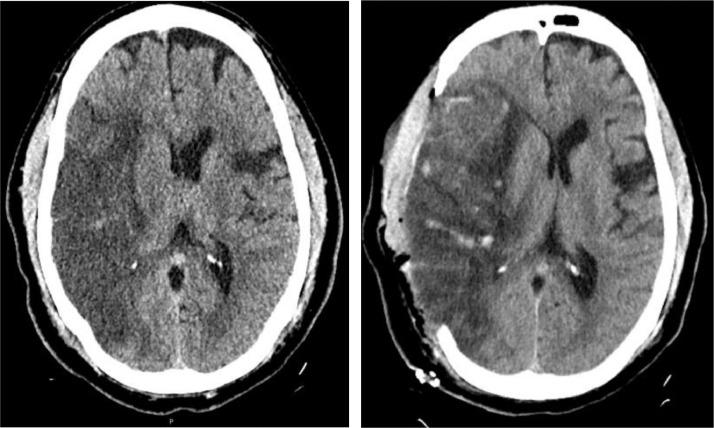

Severe acute respiratory syndrome coronavirus (SARS-CoV-2) is responsible for an unprecedented worldwide pandemic that has severely impacted the United States. As the pandemic continues, a growing body of evidence suggests that infected patients may develop significant coagulopathy with resultant thromboembolic complications including deep vein thrombosis, pulmonary embolism, myocardial infarction, and ischemic stroke. However, this data is limited and comes from recent small case series and observational studies on stroke types, mechanisms, and outcomes. Furthermore, evidence on the role of therapeutic anticoagulation in SARS-CoV-2 infected patients with elevated inflammatory markers, such as D-dimer, is also limited. We report the case of a middle-aged patient who presented with a large vessel ischemic stroke likely resulting from an underlying inflammatory response in the setting of known novel coronavirus infection (COVID-19). Histopathologic analysis of the patient's ischemic brain tissue revealed hypoxic neurons, significant edema from the underlying ischemic insult, fibrin thrombi in small vessels, and fibroid necrosis of the vascular wall without any signs of vasculature inflammation. Brain biopsy was negative for the presence of SARS-CoV-2 RNA (RT-PCR assay). Along with a growing body of literature, our case suggests that cerebrovascular thromboembolic events in COVID-19 infection may be related to acquired hypercoagulability and coagulation cascade activation due to the release of inflammatory markers and cytokines, rather than virus-induced vasculitis. Further studies to investigate the mechanism of cerebrovascular thromboembolic events and their prevention is warranted.

严重急性呼吸综合征冠状病毒(SARS-CoV-2)引发了一场史无前例的全球大流行,对美国造成了严重影响。随着大流行的持续,越来越多的证据表明,感染患者可能会出现明显的凝血功能障碍,导致血栓栓塞并发症,包括深静脉血栓形成、肺栓塞、心肌梗死和缺血性卒中。然而,这些数据有限,并且来自最近关于卒中类型、机制和结果的小病例系列和观察性研究。此外,关于在炎症标志物(如 D-二聚体)升高的 SARS-CoV-2 感染患者中使用抗凝治疗的证据也有限。我们报告了一例中年患者的病例,该患者患有大血管缺血性卒中,可能是在已知新型冠状病毒(COVID-19)感染的情况下,由潜在的炎症反应引起的。对患者缺血性脑组织的组织病理学分析显示,缺氧神经元、潜在缺血损伤引起的明显水肿、小血管中的纤维蛋白血栓形成以及血管壁的纤维样坏死,没有任何血管炎症的迹象。脑活检未发现 SARS-CoV-2 RNA(RT-PCR 检测)的存在。随着越来越多的文献报道,我们的病例表明,COVID-19 感染中的脑血管血栓栓塞事件可能与炎症标志物和细胞因子的释放导致的获得性高凝状态和凝血级联激活有关,而不是病毒引起的血管炎。有必要进一步研究脑血管血栓栓塞事件的发生机制及其预防措施。